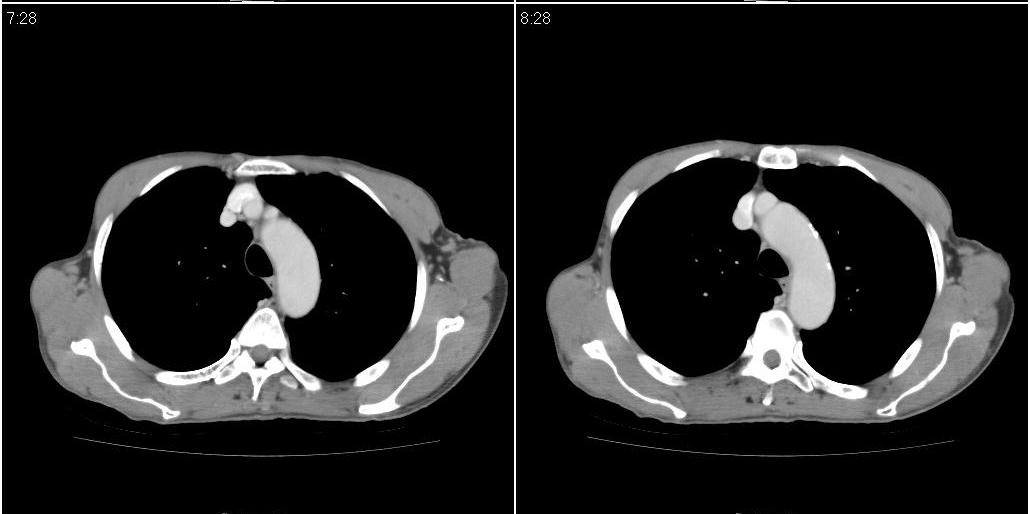

标题: ct增强:

右肺中叶阻塞性不张及肺炎,高度怀疑支气管占位,建议纤支镜检查!

考虑右肺中叶感染。左肺下叶支扩。

右中肺阻塞性炎症,建议纤支镜!双下支扩感染。

1)右肺中叶慢性炎症并支气管扩张,节段性肺不张。2)两肺下叶支气管扩张。